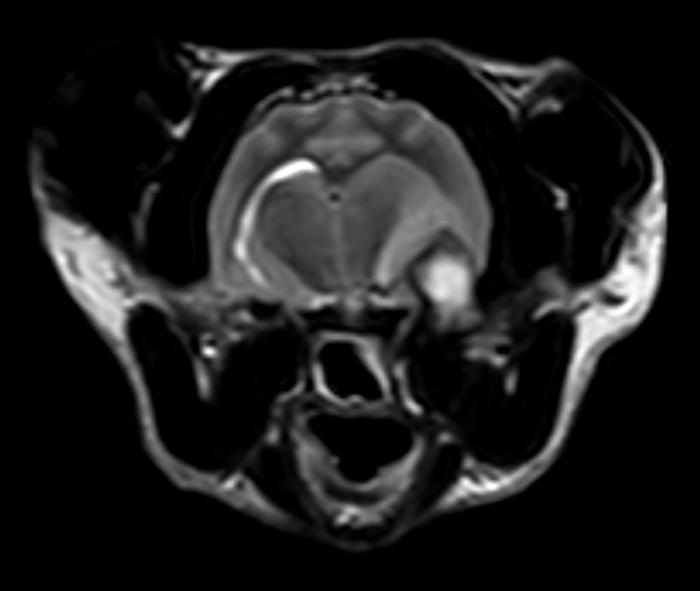

- Resonancia magnética craneal: (día 5) ocupación completa de la cavidad timpánica izquierda (Figura 1A-F) con invasión intracraneal (Figura 1A-C) con edema vasogénico y efecto masa con desplazamiento dorso-medial del lóbulo piriforme, desplazamiento contralateral de la línea media y región talámica izquierda (Figura 1A,D), colapso marcado del ventrículo lateral izquierdo (Figura 1F), y signos de herniación transtentorial e incipiente transforaminal. Se sospecha de infección intracraneal otogénica con formación de absceso en región temporal por extensión de otitis media-interna. Cabe señalar que no se visualizó contenido en las bullas timpánicas.